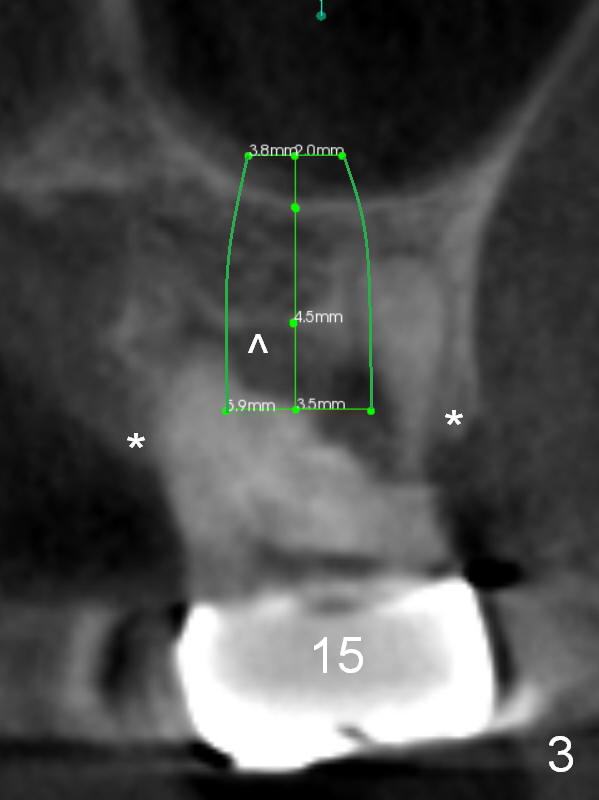

The tooth #15 of a 56-year-old man appears to be non-salvageable due to the large distal cervical caries (Fig.1 (CBCT) C). Immediately after extraction and socket debridement and antibiotic soaking, a 2 mm pilot drill is used for 4 mm, followed by 2.8 and 3.6 mm round burs for 4-6 mm (Fig.1,2 (coronal section)). At #14, the initial depth for 2 mm and 2.8 mm drills is 7 mm. The depth may increase until 9 mm (Fig.1,3). Insert parallel pins after initial osteotomies; check with surgical stent and/or take PA. After placement of allograft/Osteogen, place 4x10 and 6x8 or 10 mm implants at #14 and 15, respectively.